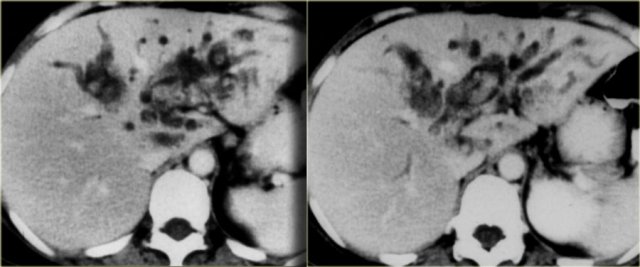

The patient on the left developed severe liver failure and a resection was performed.

Notice the intrahepatic bile duct dilatation, splenomegaly and dilated venous collaterals.

In the resected specimen there is a central dot sign (blue arrow) and a small pus collection (yellow arrow).